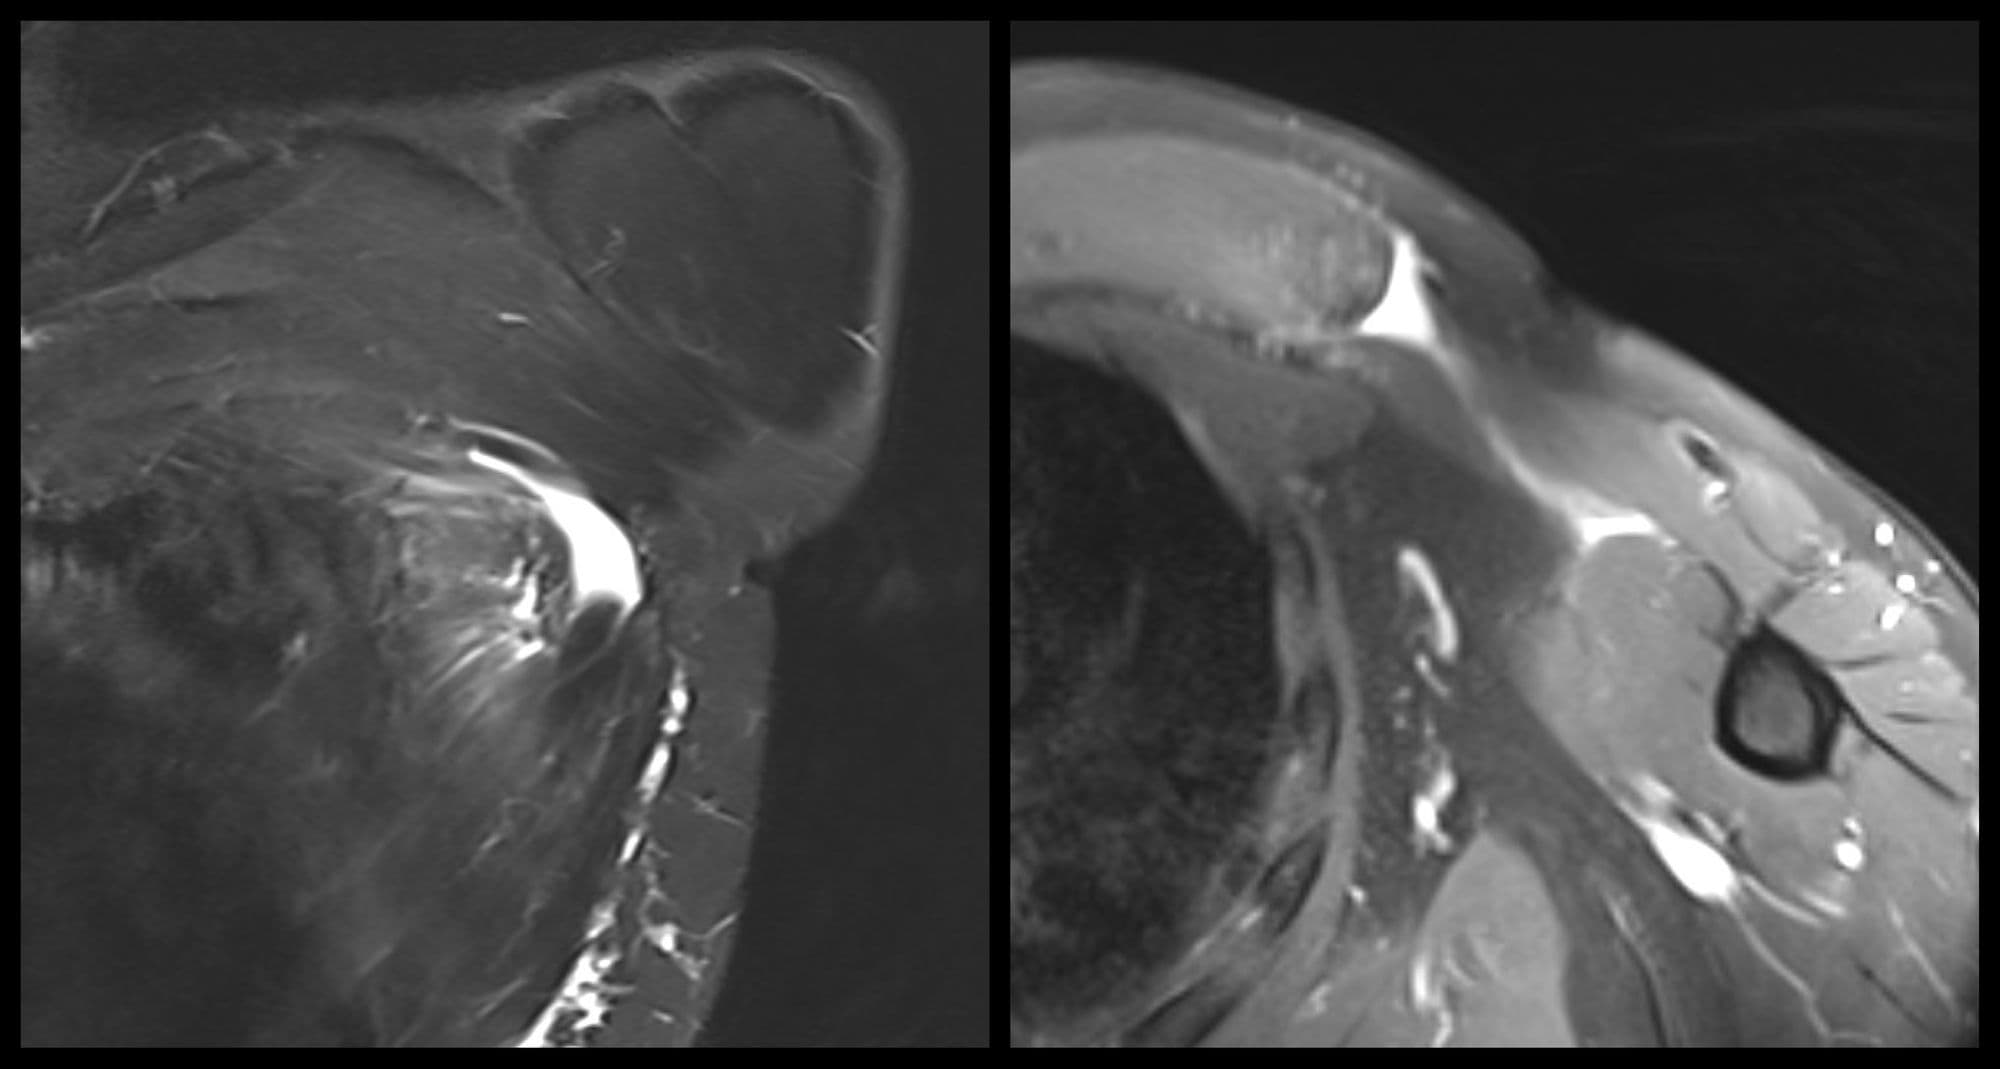

Glenoid Reconstruction with Allograft

Trauma UESports

Latarjet Procedure

Sports